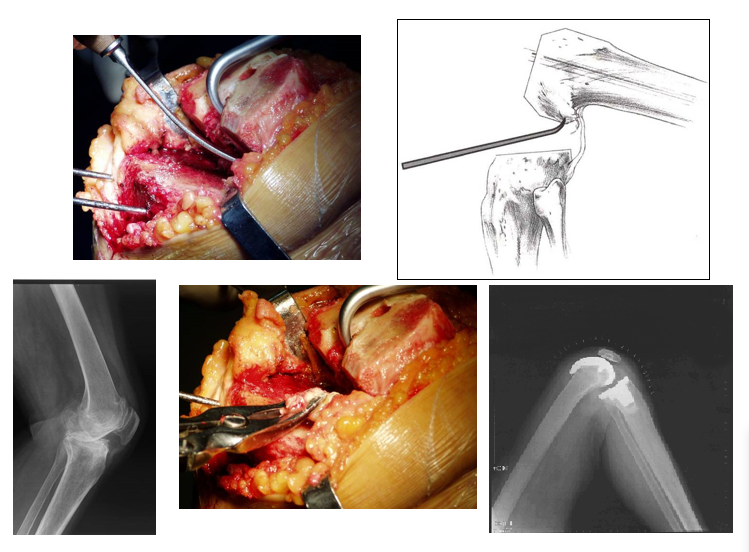

切骨与伸屈间隙

正确地切骨易于建立对称的伸屈矩形间隙

髓内与髓外定位股骨——髓内定位胫骨——髓外定位(特别胫骨弓形明显)                髓内定位(压配型髓内延长柄)

切骨顺序和切骨量先做股骨通过股骨假体相对于胫骨髓外对位装置的旋转建立屈曲间隙。先做胫骨用关节间隔垫来获得对称的平衡伸直间隙。股骨远端切骨量少于9mm避免关节线上升或伸膝间隙大

股骨髓内定位进化PCL止点上方约1cm处,常偏内几mm

股骨侧测量

• 后参照系统(最可靠)

• 恢复屈曲位的关节线

• 平衡后交叉韧带

• 减少中度屈曲时的松弛

股骨远端外翻角外翻角的确定:是髋关节中心与膝关节中心连线的垂直线髋关节内外翻会影响股骨远端外翻角髋关节外翻型5°,内翻型7°

股骨侧假体旋转对线的确定1、Whiteside线(经滑车槽轴线)2、经内外上髁连线3、后髁连线3°外旋4、通过外旋对线获得屈曲间隙对称的方法